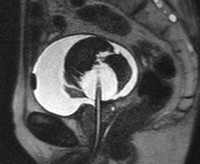

Сверток крови в мочевом пузыре